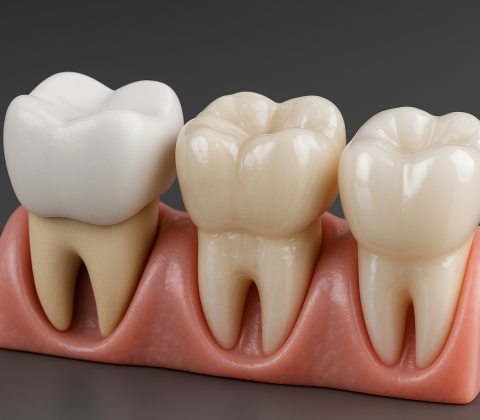

چرا بعد از عصبکشی باید روکش دندان گذاشته شود؟ آیا همیشه ضروری است؟

عصبکشی یا درمان ریشه یک مرحلهی مهم در نجات دندان آسیبدیده است، اما به تنهایی پایان کار نیست. بعد از انجام عصبکشی، دندان دیگر عصب ندا

چند وقت بعد از عصبکشی باید روکش بگذاریم؟

در بیشتر موارد، توصیه میشود که بین یک تا دو هفته پس از عصبکشی برای روکش دندان اقدام شود، اما زمان دقیق آن بسته به شرایط بالینی متفاوت اس

چند وقت بعد از عصبکشی میتوان روکش گذاشت؟

عصبکشی دندان (درمان ریشه) یکی از مراحل مهم در حفظ دندان آسیبدیده است؛ اما برای محافظت از این دندان و جلوگیری از شکستگی، در بسیاری از موا